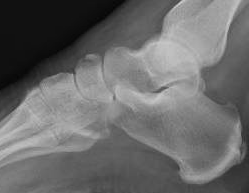

Xray

Displaced navicular stress fracture